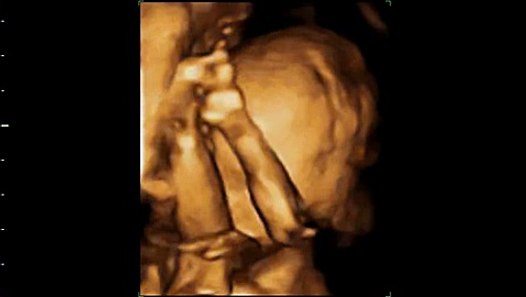

3d Ultrasound At 20 Weeks Baby Boy

Baby Boy Remy Taken By Tammy At First Glimpse Imaging In Cedar